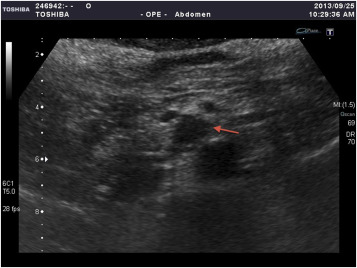

A 64-year-old woman with past medical history significant for hypertension had visited the emergency department many times over the course of several years due to intermittent hypertensive emergencies. On this presentation, she was admitted with features of symptomatic cholelithiasis. Abdominal ultrasound confirmed the presence gallstones and incidentally showed a 1.5-cm hypoechoic mass in the uncinate process of the pancreas (Figure 1 ). A physical examination was unremarkable except for mild right upper quadrant tenderness and elevated blood pressure (211/112 mmHg). Serum carcinoembryonic antigen and carbohydrate antigen 19-9 levels were both within normal limits. Contrast-enhanced computer tomography showed a 1.6-cm enhancing mass in the uncinate process of the pancreas (Figure 2 ). On magnetic resonance imaging, the lesion was identified as a 1.6-cm low-intensity mass on T1-weighted imaging and a slightly high-intensity mass on T2-weighted imaging. Magnetic resonance imaging with contrast enhancement revealed that the lesion was enhanced (Figure 3 ). On the basis of these findings, preoperative diagnosis was a pancreatic hypervascular tumor, suspected to be a neuroendocrine tumor. A pylorus-sparing Whipple procedure was recommended to achieve complete excision of the tumor and to treat the symptomatic cholelithiasis. Grossly, an oval and well encapsulated tumor measuring 1.5 cm in greatest dimension was noted within the lower part of uncinate process. Microscopically, this well-encapsulated tumor was composed of proliferation of polygonal cells arranged in trabecular, nest, and alveolar patterns separated by a stroma rich in vascular network. The tumor cells had an amphophilic-to-basophilic cytoplasm. Tumor nuclei were round to oval with moderate nuclear pleomorphism and prominent nucleoli (Figure 4 ). Mitotic figures were not identified. Capsular and vascular invasion was not present. By immunohistochemical staining, the tumor cells were reactive to CD 56, synaptophysin, and chromogranin A. The sustentacular cells surrounding the tumor clusters were also highlighted by immunostaining for S100. The lymph nodes dissected were free of malignancy. Both histomorphology and immunoprofiles of the tumor were typical of paraganglioma. Hypertensive urgency developed after the operation which was controlled with continuous intravenous nicardipine. Collected 24-h urine catecholamine data showed that norepinephrine levels were 175 μg/day (normal value: <97 μg/day) and vanillylmandelic acid levels were 8.06 mg/day (normal value: 1–7.5 mg/day). After 7-day nicardipine treatment, we gradually shifted to oral antihypertensive agents. Finally, the patient was successfully discharged with oral doxazosin (4 mg) one tablet per day. The patient had no clinical signs, symptoms, or family history suggestive of multiple endocrine neoplasia or Von Hippel–Lindau disease.

Figure 1. Transabdominal ultrasonogram demonstrated a hypoechoic mass (arrow) in the uncus of the pancreas. |